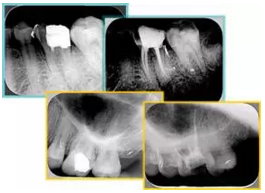

2. X 線片

共有 4 張 X 線片,分別是術(shù)前、診斷絲 、主牙膠尖確認(rèn)、術(shù)后。

( 1 )術(shù)前:術(shù)前 X 線片用來了解牙齒的大概情況。術(shù)前預(yù)期為多根牙時 X 線片應(yīng)偏頭拍攝。

( 2 )診斷絲:根據(jù)術(shù)前 X 線片進(jìn)行開髓、根管的初步預(yù)備后,需要插入診斷絲,用來指示工作器械位置。常用 10 號或 15 號擴(kuò)大器作為診斷絲插入牙髓腔。

( 3 )主牙膠尖確認(rèn):通過術(shù)前預(yù)期和診斷絲診斷,明確工作長度、牙根走向,進(jìn)行根管預(yù)備。之后應(yīng)進(jìn)行主牙膠尖(中銼)確認(rèn),已明確根管是否適合充填。

( 4 )術(shù)后:觀察治療效果。